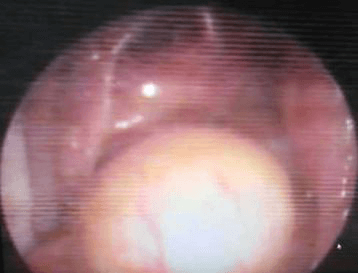

2012 সালের অক্টোবরে তিনি আমাদের কাছে ফিরে এসেছিলেন, ধীরে ধীরে প্রগতিশীল ডান-পার্শ্বযুক্ত নাক ব্লক, ফুসফুস অনুনাসিক স্রাব এবং মাঝে মাঝে 2-বছরের মাথাব্যথার অভিযোগ করেছিলেন। এপিস্ট্যাক্সিস বা অন্যান্য ইএনটি অভিযোগের কোন ইতিহাস ছিল না। পরীক্ষায়, নাকের ডান দিকে মসৃণ পৃষ্ঠ ভরাট করে একটি বড় ভর ছিল, স্পর্শে রক্তপাত হয়নি। এবং একটি স্থূল DNS বাম. মস্তিষ্কের এমআরআইতে দেখা গেছে যে একটি মিশ্র তীব্র ক্ষত মাথার খুলির স্ফেনয়েড, ইথময়েড সাইনাস এবং সেলা এবং ক্লিভাসের অংশে অনুপ্রবেশ করে। সমস্ত রুটিন রক্ত এবং প্রস্রাব তদন্ত স্বাভাবিক ছিল. ক্ষতের বায়োপসি ইনভার্টেড প্যাপিলোমার পুনরাবৃত্তির পরামর্শ দিয়েছে। তিনি টিউমারের এন্ডোস্কোপিক ডিবুলিং করান। HPE এই সময় hemangiopericytoma পরামর্শ ছিল.

তিনি প্রথমে যশোদা হাসপাতালে ওপি হিসাবে এবং পরে স্থানীয় ইএনটি-এর সাথে অনুসরণ করেছিলেন। দুই বছর পর তার আমাদের সফরের সময় পুনরাবৃত্তির কোনো প্রমাণ পাওয়া যায়নি। এখন তিনি এপ্রিল মাসে আমাদের কাছে উপস্থাপন করেছিলেন যে এক সপ্তাহের জন্য ডান দিকের নাক দিয়ে রক্তপাত হচ্ছে। DNE ডানদিকে একটি অনিয়মিত মসৃণ পৃষ্ঠ ভাস্কুলার ভর দেখিয়েছে। CT PNS অনুনাসিক গহ্বরের পিছনের অংশে নরম টিস্যু ভর দেখায় যা ছাদ পর্যন্ত প্রসারিত হয় (ক্রিব্রিফর্ম প্লেট) এবং উপরে স্ফেনয়েড সাইনাস এবং নীচে নাসোফ্যারিনক্স পূরণ করে। তাকে রেডিওথেরাপি বিভাগে রেফার করা হয়েছিল যেখানে তাকে মস্তিষ্ক এবং কক্ষপথের নৈকট্যের কারণে IMRT-এর পরামর্শ দেওয়া হয়েছিল।